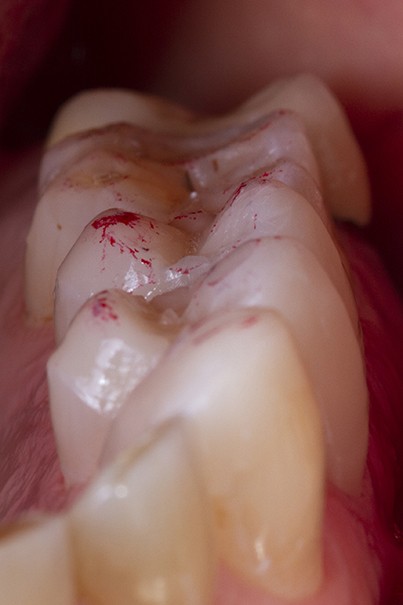

Un sablage à l’oxyde d’alumine est recommandé lorsque les usures sont marquées afin de préparer la surface de collage. Après rinçage, un mordançage à l’acide orthophosphorique est réalisé pendant 30 secondes sur l’émail et 15 secondes sur la dentine. Après un rinçage scrupuleux, un adhésif est étalé sur l’ensemble des surfaces mordancées, soufflé puis photopolymérisé (fig. 5).